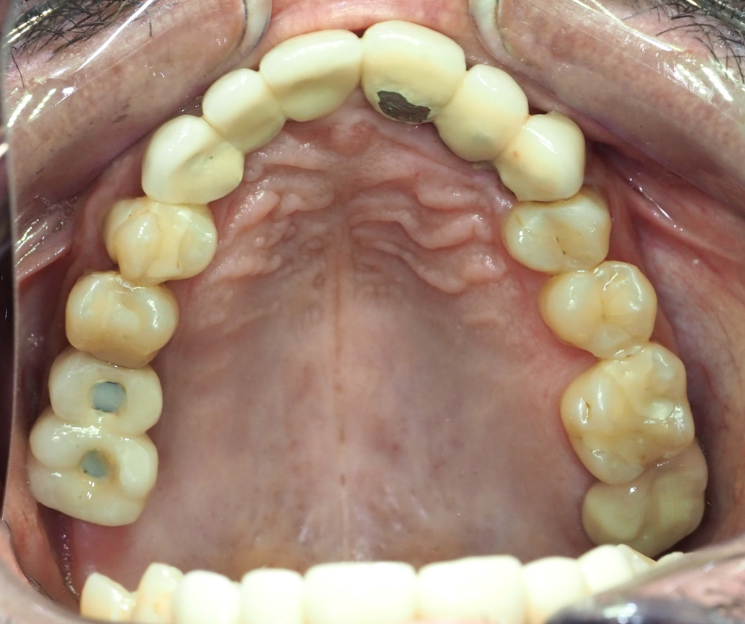

Paciente con infecciones de origen dental que comprometían severamente el hueso alveolar en la zona anterior superior. Se realizó la extracción de los dientes 21, 22 y 23, y se optó por una rehabilitación inmediata mediante implantes córticobasales.

Esta combinación permitió anclar los implantes en hueso cortical, que mantiene su estabilidad incluso en presencia de procesos infecciosos en el hueso alveolar. El resultado: rehabilitación funcional y estética el mismo día de la cirugía.